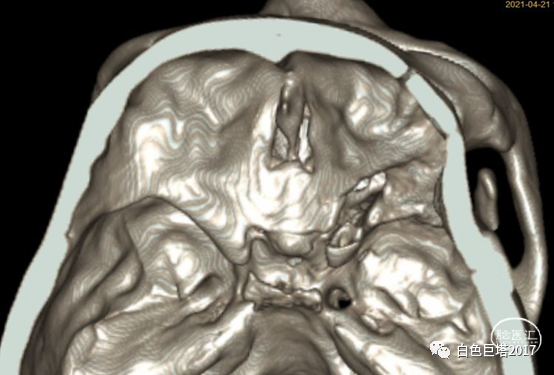

入院头颅CT检查提示右侧颞骨-眼眶后外侧壁骨质改变,眶内未见明显占位。报告考虑骨纤维异常增殖症可能性大。

3Dslicer重建可见眶后外侧壁骨质不均匀增厚,毛糙。